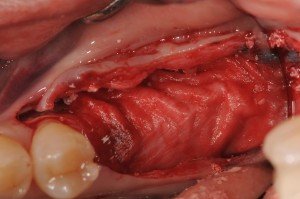

歯槽頂にGBRするために、インプラントは浅く埋入し、出血を促すためのデコルチケーションをしています。

Bi0-ossと自家骨を混和して、歯槽の形態を整えます。

Bi-ossとのゴールデンコンビのBio-guideを用い、十分な減張切開を加えたのちに縫合します。